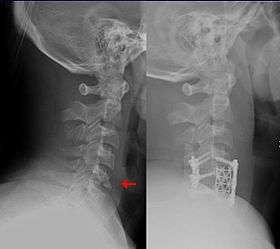

Flexion teardrop fracture

Teardrop fracture of the cervical spine before and after treatment with metal fixation

A flexion teardrop fracture is a fracture of the anteroinferior aspect of a cervical vertebral body due to flexion of the spine along with vertical axial compression.[1] A teardrop fracture is usually associated with a spinal cord injury, often a result of displacement of the posterior portion of the vertebral body into the spinal canal.[2]